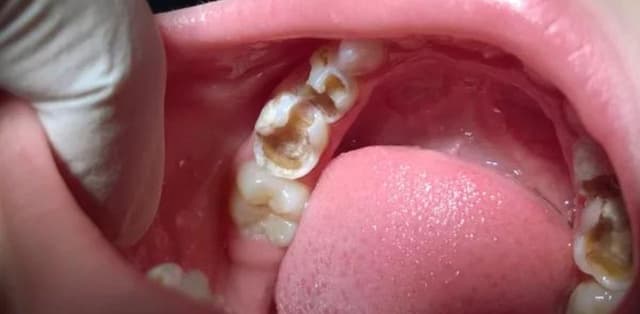

Tác nhân khiến răng sâu nặng và giải pháp từ chuyên gia

Điều trị sâu răng là vấn đề mà mọi người bệnh đều phải đau đầu mỗi khi nhắc đến. Ấy vậy, không phải việc điều trị lúc nào cũng diễn ra suôn sẻ, sẽ vẫn có những khi tình trạng răng sâu nặng hơn trước và đôi khi chữa xong răng này lại đến răng […]